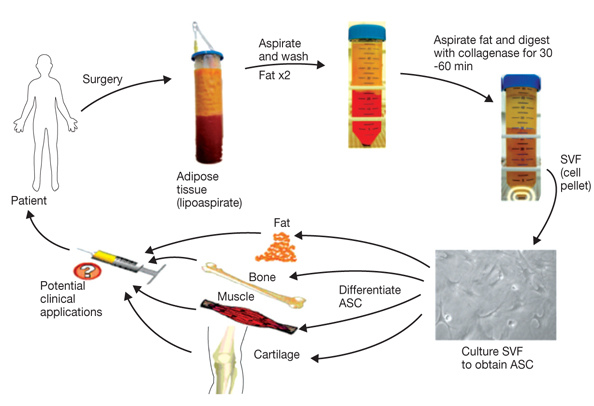

- B. T. Estes, B. O. Diekman, J. M. Gimble, and F. Guilak, “Isolation of adipose-derived stem cells and their induction to a chondrogenic phenotype,” Nature Protocols, vol. 5, no. 7, pp. 1294–1311, 2010. View at Publisher · View at Google Scholar · View at Scopus

- P. A. Zuk, M. Zhu, H. Mizuno et al., “Multilineage cells from human adipose tissue: implications for cell-based therapies,” Tissue Engineering, vol. 7, no. 2, pp. 211–228, 2001. View at Publisher · View at Google Scholar · View at Scopus

- V. Zachar, J. G. Rasmussen, and T. Fink, “Isolation and growth of adipose tissue-derived stem cells,” Methods in Molecular Biology, vol. 698, pp. 37–49, 2011. View at Publisher · View at Google Scholar · View at Scopus